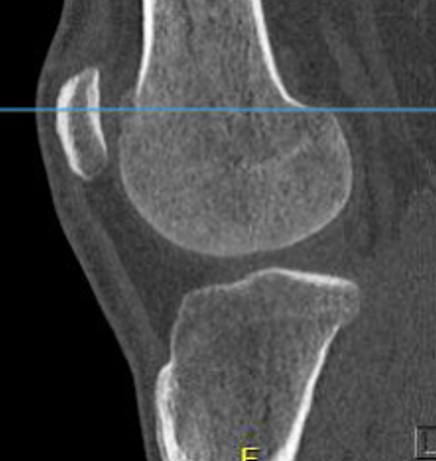

CT

Best investigation

- lucent nidus surrounded by dense bone

Osteoid osteoma femur